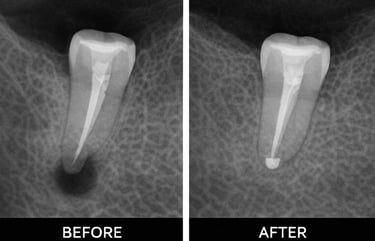

Examination & X-rays – determine the extent of infection or damage

Root canal treatment removes infected or damaged pulp from inside a tooth. The pulp contains nerves and blood vessels, and infection can cause pain, swelling, or abscesses. During the procedure, the dentist cleans out the infection, shapes the root canals, and fills them with a safe material. Finally, the tooth is restored with a crown or filling to protect it. Root canals prevent infection from spreading and help keep your natural tooth